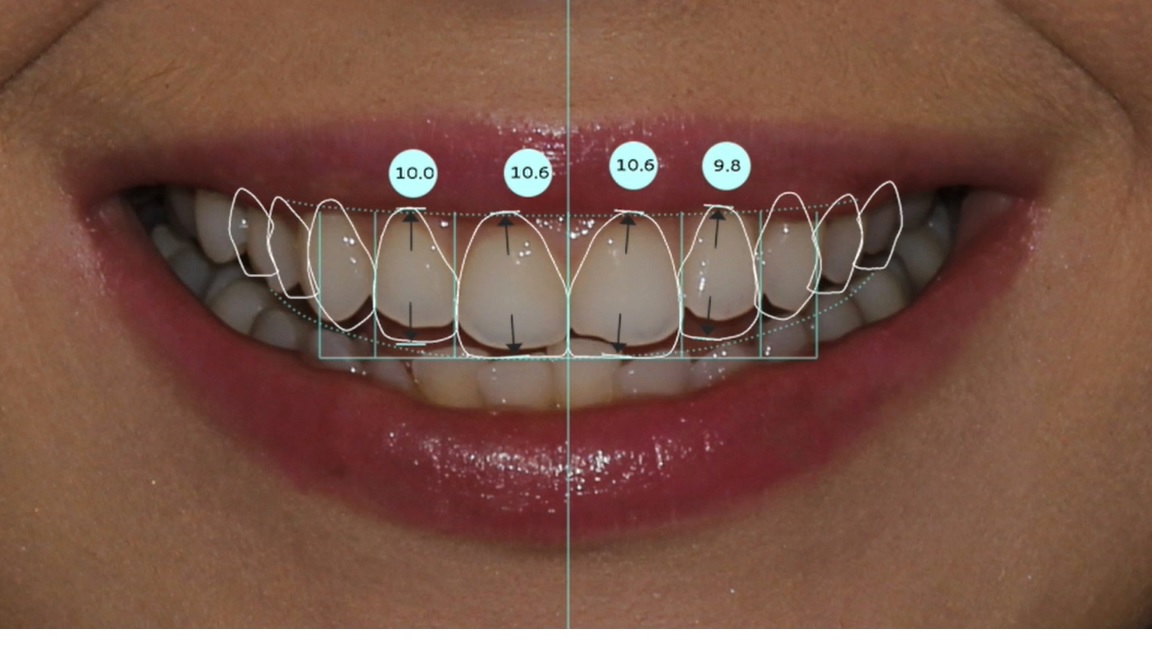

Belirlenen yeni diş yapısı ve dental oranlara göre gülüş tasarım yazılımı, planlanan tedavinin bitmiş halinin sanal görüntüsünü oluşturur. Bu görüntü üzerinde, hastanın da istek ve düşünceleri dikkate alınarak gerekli düzeltmeler yapılır.

Son hali verilen dijital gülüş tasarımı üzerinde dijital ölçümler yapılarak veya doğrudan Cad-Cam cihazlar kullanılarak dijital planlama , Mock-up adı verilen reel tasarıma dönüştürülür. Daha sonra, Mock-up tasarım, ağıza aktarılarak geçici dişler üretilir. Bu aşamada , yüz-dudak ve alt-üst dişlerin birbirleriyle uyumları ile diş renk ve boyutları, dişeti konturları detaylı olarak tekrar değerlendirilir. Bu değerlendirmeler sonrasında Mock-up üzerinde gerekli son düzenlemeler yapılıp protetik işlemlere geçilir. Bu iş akışı neticesinde elde edilen estetik sonuç, dijital tasarım ve Mock-up çalışması ile oldukça uyumludur.